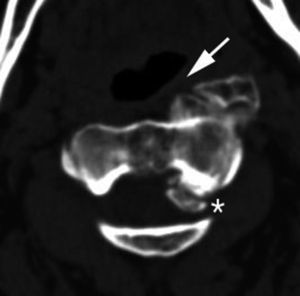

Depósitos de pirofosfato cálcicoLos depósitos de pirofosfato cálcico (CPPD) pueden verse en varias estructuras, como los discos intervertebrales, ligamentos, bursas, cartílago articular, sinovial y cápsulas articulares. Es frecuente su localización en la articulación atlanto-axoidea, donde se puede depositar en el ligamento transverso y sinovial, y asociar una artropatía erosiva. Se asocia con aumento de partes blandas retrodontoideas (fig. 15, fig. 15b online)41.